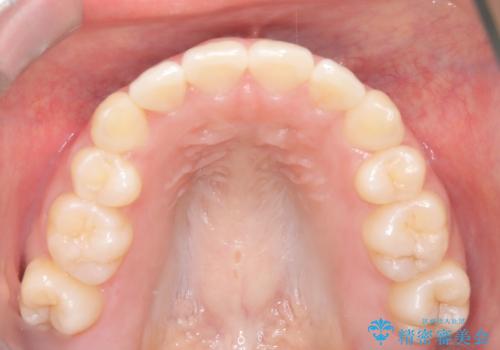

- 1年1ヶ月

奥歯の噛み合わせは綺麗に噛んでいたため、前歯の叢生(でこぼこ)を、短期間で治療完了するように計画しました。

前歯のガタツキを改善する治療法として、マウスピース矯正が適していることが多いです。

マウスピース矯正は、金属製のブラケットやワイヤーを使用せずに、透明なマウスピースを装着して歯を移動させる方法です。そのため、目立たず、痛みも少ないです。